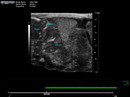

Caption Play MovieUltrasound imaging of mutant 2362-004 (E16.5) in the sagittal view shows the heart out of the chest, suggesting ectopia cordis